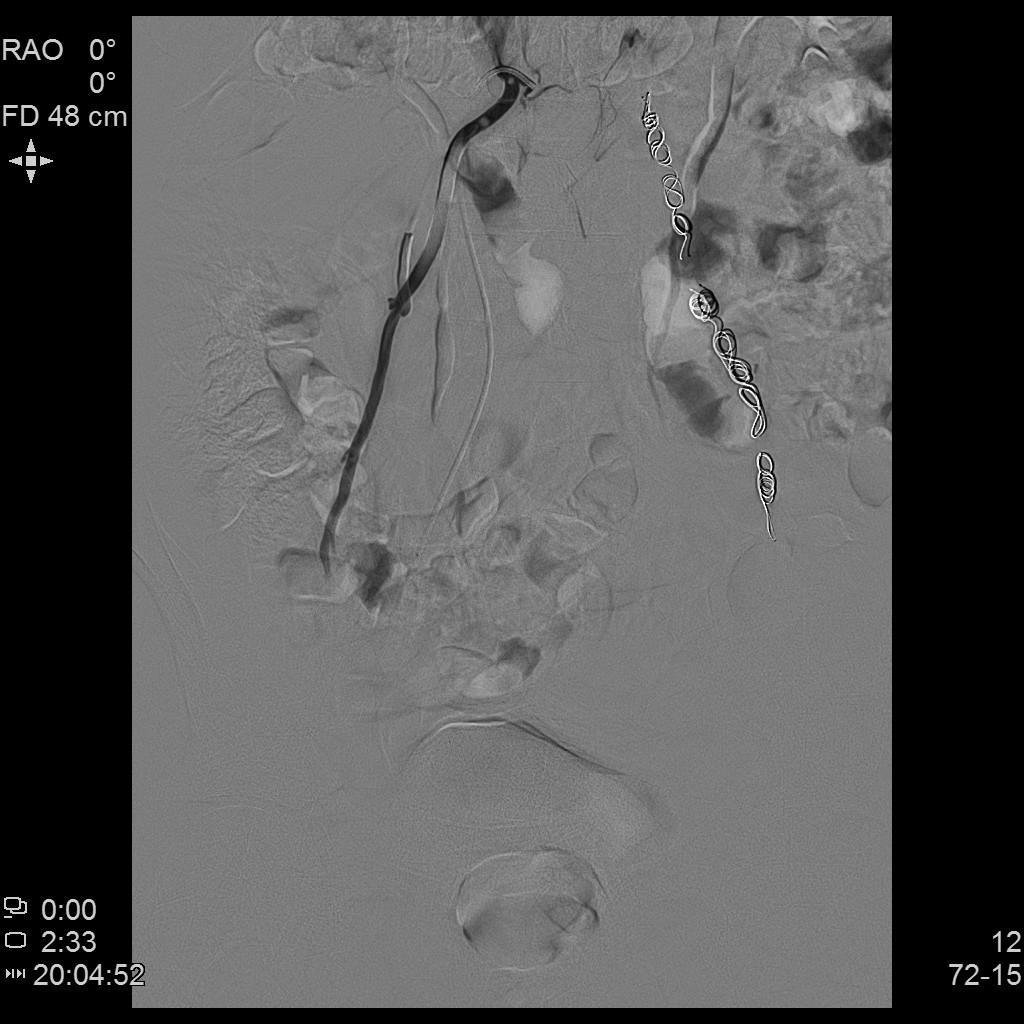

- 行左侧精索静脉造影显示左侧精索静脉明显扩张、迂曲,血流逆流。予以超选插管至左侧精索静脉中下段行弹簧圈栓塞+泡沫硬化栓塞治疗。复查造影显示左侧精索静脉主干闭塞。

左侧精索静脉介入硬化栓塞

右侧精索静脉介入栓塞